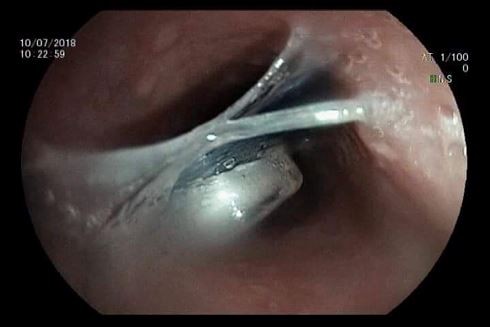

Hình ảnh dị vật mắc trong thực quản bệnh nhân

Tại bệnh viện, bệnh nhân V.T.M đã được ê kíp bác sĩ thăm khám, chụp X quang vùng thực quản nghi ngờ có dị vật chưa rõ loại tại thực quản đoạn ngang đốt sống cổ C4.- C5. Sau khi hội chẩn, ê kíp bác sĩ đã tiến hành cho bệnh nhân nội soi thực quản an thần để gắp dị vật. Chỉ sau 30 phút thủ thuật, bác sĩ đã gắp thành công dị vật là một vỉ thuốc còn nguyên vỏ với các cạnh sắc nhọn, đường kính khoảng 2,5cm.